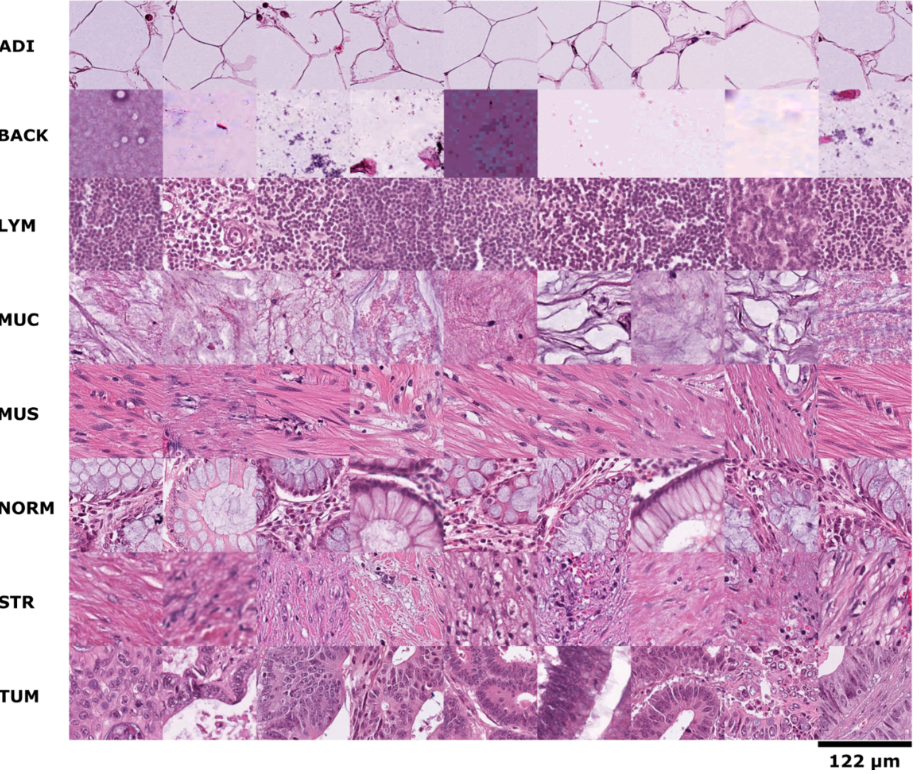

TCGA데이터는 WSI(Whole Slide Image)로 데이터 사이즈가 상당히 큰 편이다. 전부 분석하기에는 현실적으로 어렵고 이미지를 쪼개서 분석하는 방법을 취할 것이다.

사진 이미지를 (patch X patch)로 나누어 image_split_list에 저장한 후에 활용한다.